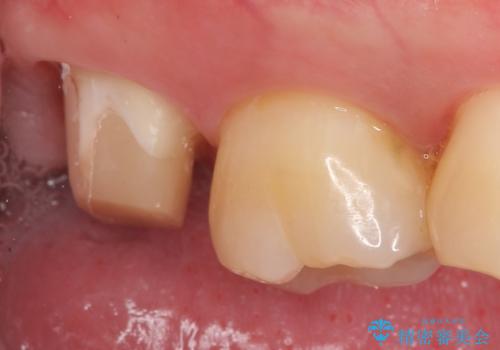

- 右上7の虫歯が大きく、他院にて抜歯と言われたが、なんとか残せないかと当院にいらっしゃった方の症例です。

自発痛の既往および持続痛を認めたため、カリエス除去後根管治療を行いました。

その後オールセラミッククラウンによる補綴を行いました。